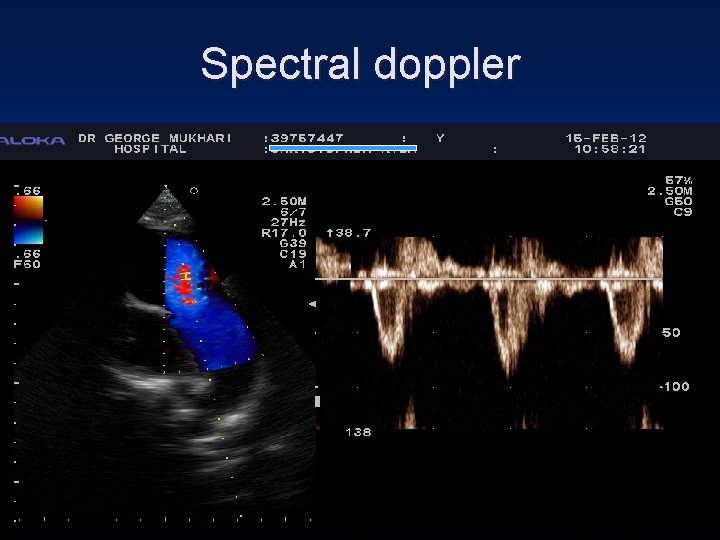

Spectral doppler

Colour flow doppler • Jet area index to LA • Vena contracta width RV RA LA